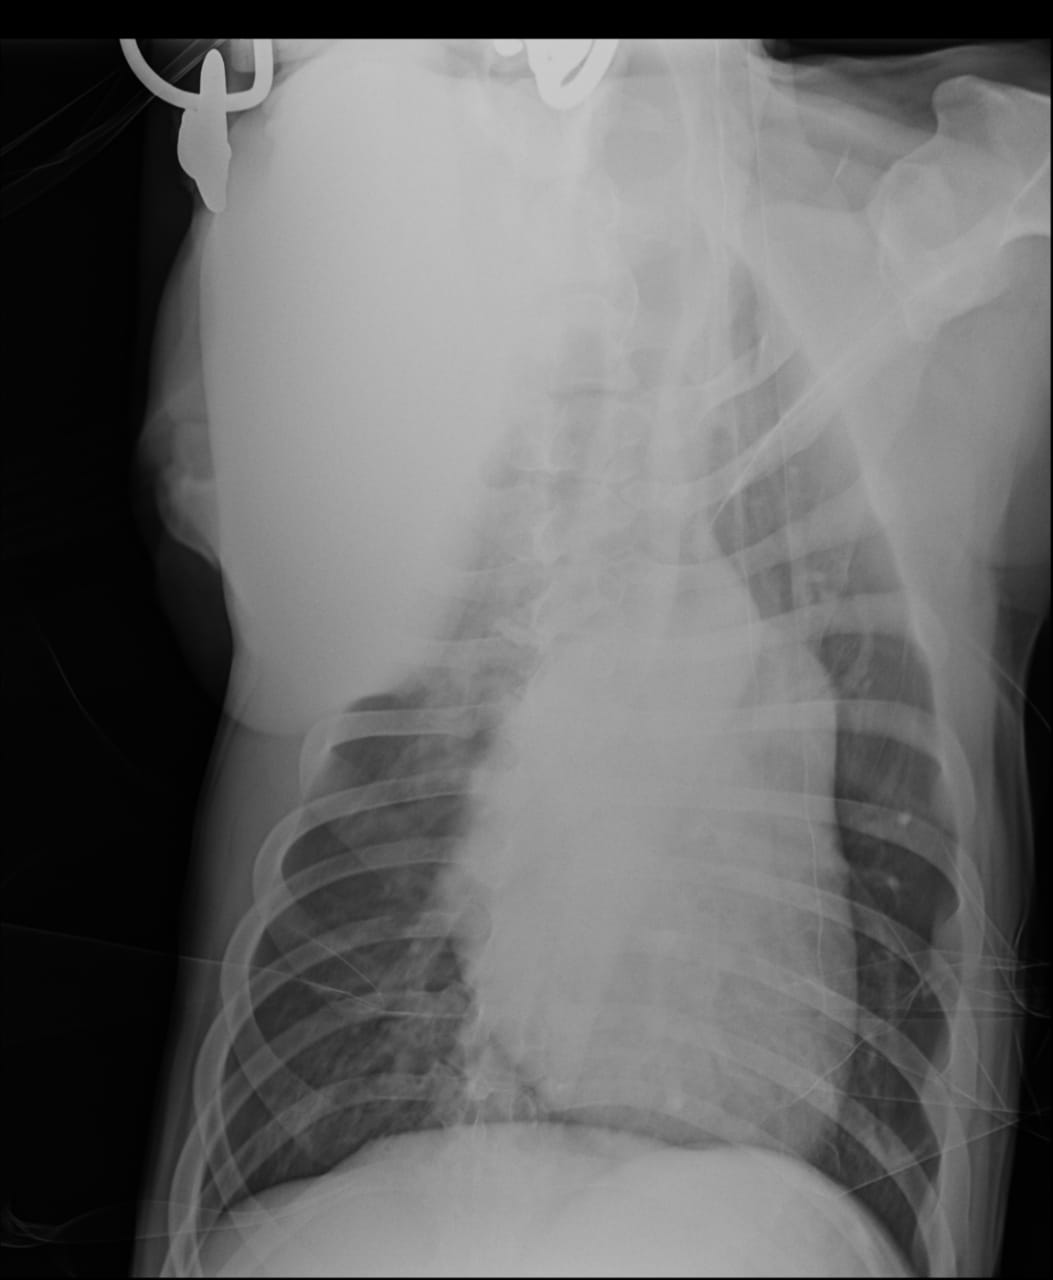

Сегодня Арчуна Ирина возила на рентген легких и сдали анализ мочи. Результат анализа мочи готов будет завтра. Рентген легких выставляю.

Ирина, ждем твоего вердикта по рентгена и можно ли нам готовить Арчи к операции по глазам.

Антибиотика курс пропили.

Лучше чем было, но явно не норма:(